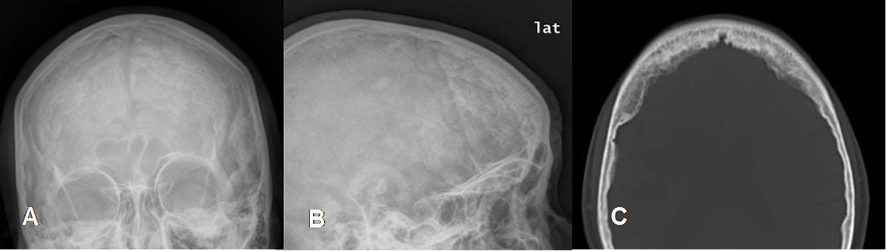

Fig 102 B. Displasia fibrosa.

A: Rx AP y B: lateral y C: TAC axial. Esclerosis y engrosamiento de los huesos frontales, con apariencia de vidrio esmerilado, por displasia fibrosa cráneofacial.